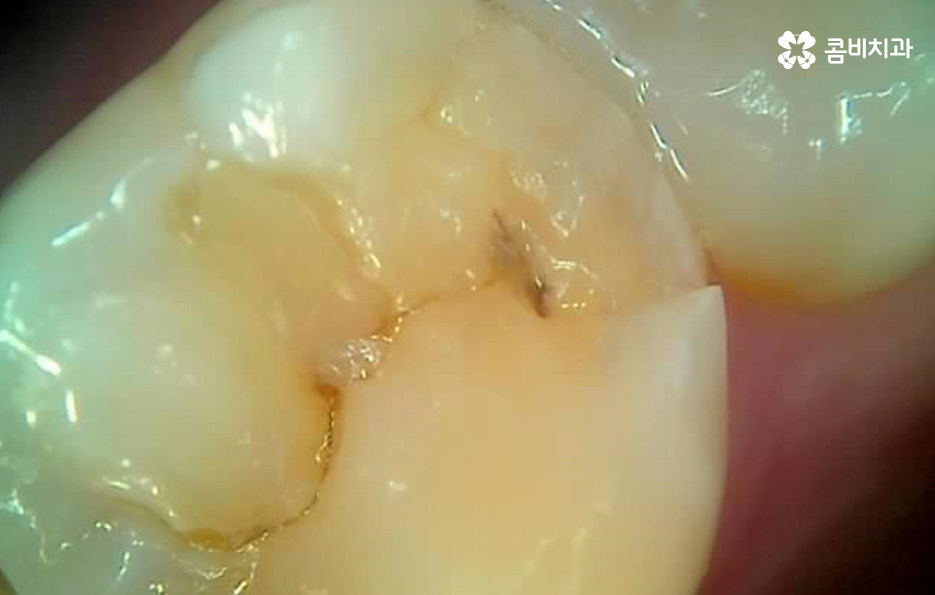

어금니 레진으로 치료 했던 부위의 주변에 검게 변색되었어요. 그리고 주변이 깨졌어요

레진은 주로 치아의 초기 손상에 활용되는 치료라는 점에서 레진 자체가 깨지거나 주변 치아가 깨지고 변색이 되더라도 당장 큰 통증을 못느끼는 경우도 많이 있어요

어금니 레진 치료 후에 레진 자체가 깨지거나 주변 치아가 깨진 경우에는 당장 안아파도 치과에서 재치료를 받는 것이 추가적인 파절을 예방하고 치아 내부로 충치가 발생되는 것을 예방할 수 있으며 특히 주변이 검게 변색되는 경우에는 착색인 경우도 있지만, 2차 충치가 이미 진행된 경우가 많기 때문에 통증과는 무관하게 치과 방문을 권하고 있어요